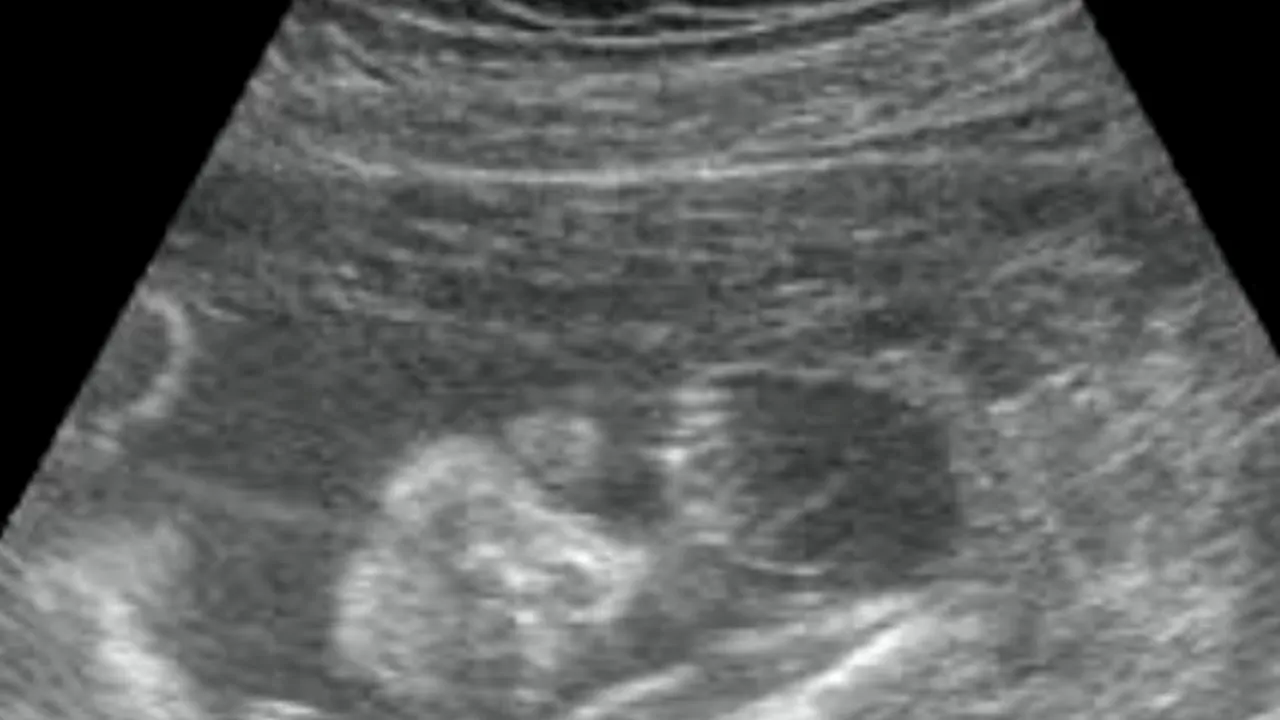

Surpriză de proporții pentru un cuplu din Marea Britanie. Chantel Pinchon, o tânără de doar 20 ani, a născut tripleți identici, fete, fără a face vreun tratament, medicii spunând că un astfel de caz se întâlnește la 200 de milioane. Femeia, care mai are un băiețel care abia a împlinit nouă luni, a declarat că „a fost un adevărat șoc” pentru ea și soțul el însă sunt fericiți că fetițele sunt sănătoase.

„A fost un adevărat șoc pentru noi să aflăm că avem tripleți, mai ales că sarcina nu era deloc programată. Acum suntem fericiți. Fetițele sunt sănatoase”, a declarat ea, potrivit The Sun.